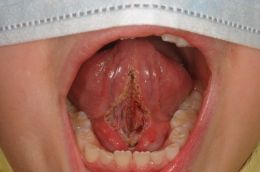

.... da una logopedista che collabora con lo studio. La frenulectomia e' stata realizzata con Laser KTP in emissione pulsata, in collaborazione con il Dott. V. Quinzi. Vengono mostrate le foto prima dell'intervento, dopo e a distanza di 2 settimane! La guarigione e' avvenuta con successo con grande fuzionalita' linguale; osservate gli ultimi residui di fibrina della tipica guarigione da laser.